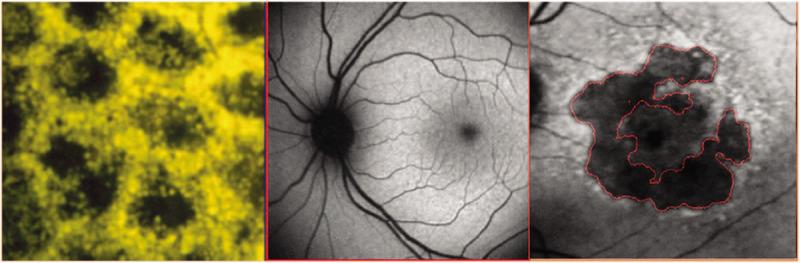

Petrukhin designed his therapeutic strategy based on a long-observed phenomenon in patients with atrophic AMD and Stargardt disease. Their retinas tend to have an accumulation of lipofuscin, a yellow-brown lipid-based substance associated with aging. Granules of lipofuscin accumulate in a retinal layer called the retinal pigment epithelium (RPE), which supports the health of light-sensing photoreceptors. In both atrophic AMD and Stargardt disease, vision loss occurs when photoreceptors die, but their death happens secondary to the loss of RPE cells. Petrukhin and others hypothesized that reducing harm from lipofuscin might prolong RPE and photoreceptor survival.

As lipofuscin accumulates in the retinal pigment epithelium, photoreceptors degenerate, which leads to vision loss. LBS-008 reduces the production of A2E, which is a toxic component of lipofuscin. Credit: National Eye Institute

Left. Retinal pigment epithelium (RPE) bis-retinoids form complex granules known as lipofuscin, which increase with age, and glow gold under blue light. Middle. Normal gray scale fundus autofluorescence (FAF) image. Right. FAF image of a patient with the dry form of age-related macular degeneration. Credit: Asia Pac J Ophthalmol (Phila). 2020 May-Jun; 9(3): 269–277. Published online 2020 Jun 1.

The best studied toxic component of lipofuscin is the bisretinoid A2E, a by-product of the normal visual cycle, the vital biochemical pathway that regenerates visual pigment, and is important for converting light (photons) into electrical signals sent from the retina to the brain.